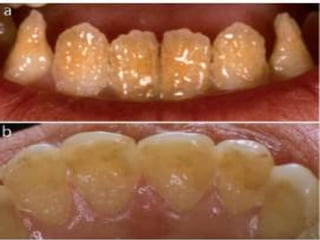

– Severe disturbances in enamel and dentin formation of

deciduous teeth

• Dental Defects: Rudimentary teeth, Congenitally absent

teeth, Hypoplastic teeth, Absence of enamel on crowns